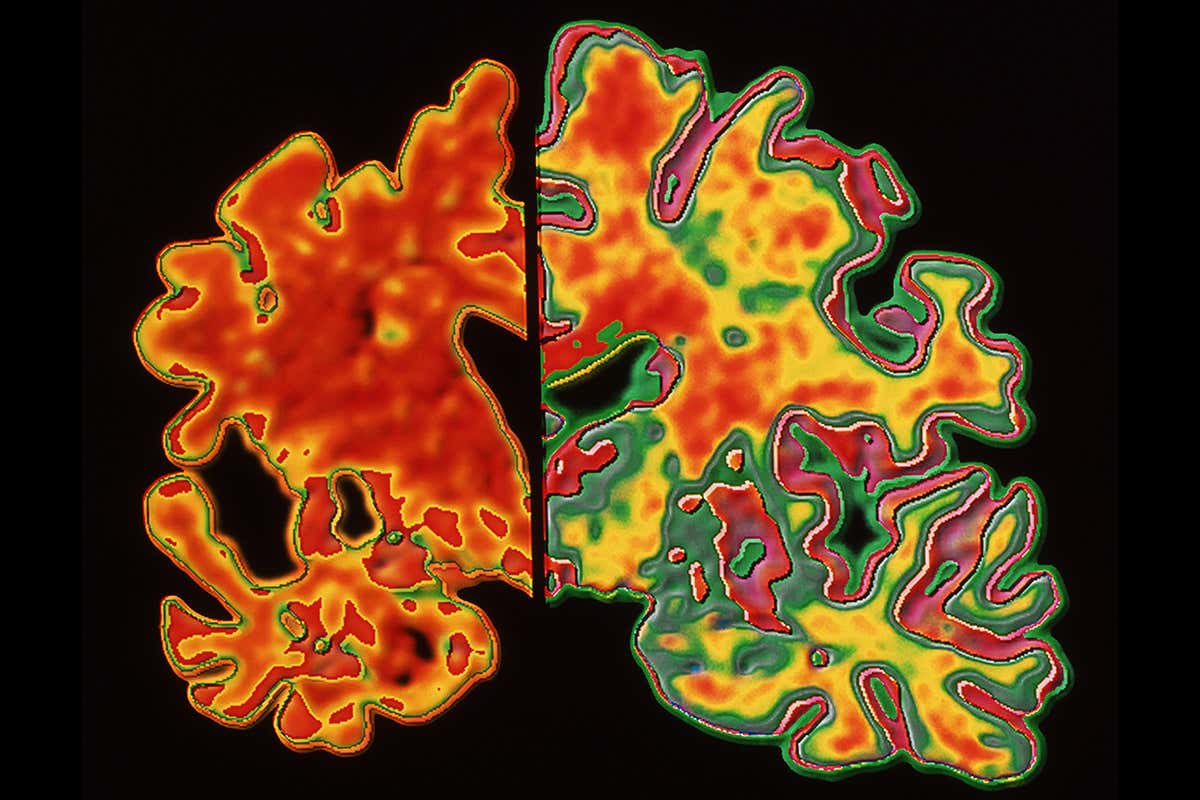

Eliminating the brain plaques associated with Alzheimer’s (seen here in the left-hand scan, with a healthy brain on the right) could help us understand the role they play Alfred Pasieka/Science Photo Library

IT’S more than a century since Alois Alzheimer first noticed and reported sticky plaques in the post-mortem brain of a patient with what we now know to be Alzheimer’s disease, yet the jury is still out on whether the plaques actually cause the disease. We might soon have a better idea: a new drug appears to be the first to harmlessly switch off production of plaque in the human brain. Further trials due to end next year and beyond might show if that halts the disease.